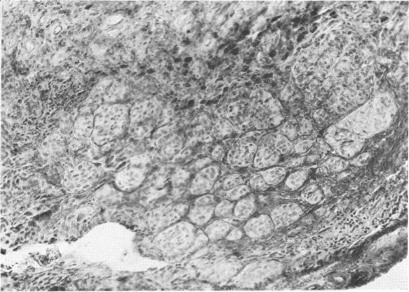

Heath P

Trans Am Ophthalmol Soc. 1951;49:147-66.